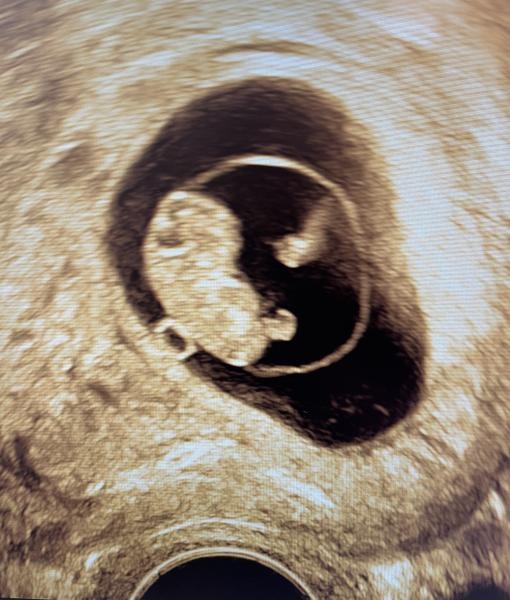

Enligt app och ägglossning 8+2 enligt vul idag 8+6. Nu syntes de små armar och ben på klumpen.

Men lilla bönan! Så söt hen är, en liten dinosaurie:D okej vad fort det går. jag är i vecka 18 idag (helt sjukt) och ska på RUL den 15de, längtar så!

Haha ja ser ut som en liten t-rex.